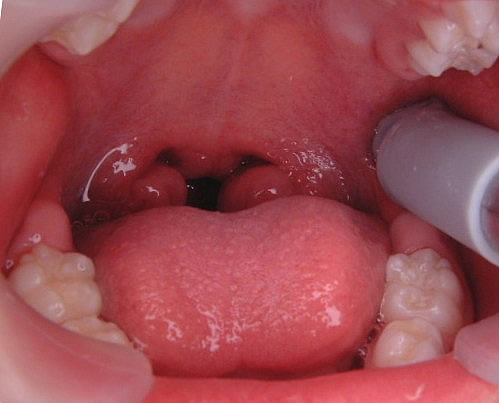

最近、口をポカ~ンとあけている子どもや若者が気になってしかたがない。そんな子どもが以前より増していると思う。口呼吸をしている子どもの口唇は、厚かったり、上唇が山型をしているのですぐわかる。それに、歯肉が硬く腫れている。

(図1)

口呼吸性の歯肉炎

口呼吸性の歯肉炎だ。プラークの付着による歯肉炎とは異なり、歯を磨いても治らない。外気がそのまま、歯肉に当たるので肥厚するのだ。さらに、扁桃腺を見てみると、腫れている子が多い。